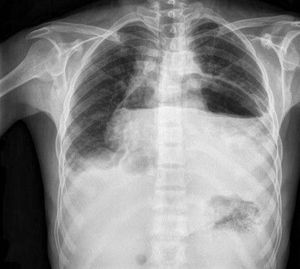

A 37-year-old man on regular haemodialysis for end-stage renal disease presented with progressive dyspnoea and orthopnoea 4 days after nephrectomy to control hypertension. What is the cause of this abnormal chest radiograph? A) Gastric torsion B) Achalasia C) Pneumopericardium D) Hiatal hernia

First of the chest x-ray don't seen marker of right and left ........the left side of loss the lung volume this case a pneumopericardium

You can see the gastric bubble, of the fundus portion of the stomach on the left side.